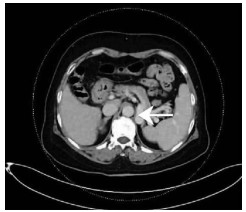

Ampullary mixed neuroendocrine/non-neuroendocrine tumor: A case report

Yannan CAO, Yuelei HU, Guoyue LYU, Zhongqi FAN

2021, 37(4): 918-920. DOI: 10.3969/j.issn.1001-5256.2021.04.041

Abstract(1012) HTML (269) PDF (2128KB)(34)

Abstract: